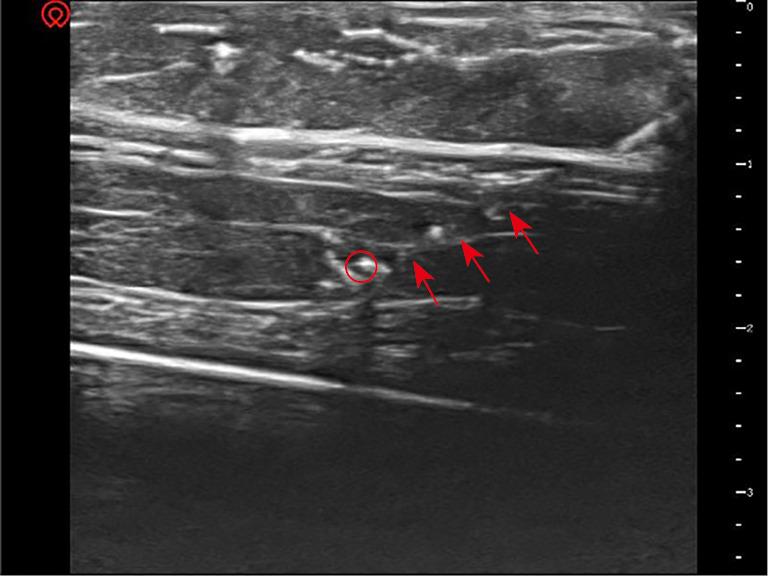

Excellent needle visualization is critical for the safety and success of ultrasound-guided puncture procedures. However, optimal visualization is often challenging when a needle is inserted at a steep angle via in-plane technique. We hypothesized that a water cushion filled under the probe would result in better needle visualization via artificial beam steering during the ultrasound-guided in-plane technique. We simulated human soft tissue with pork and two targets with rigid needles. A water cushion was also made beforehand: a surgical glove was filled with an appropriate amount of water. Ultrasound-guided in-plane puncture procedures for the two targets were performed without and with the water cushion under the ultrasound probe. Clear ultrasound images of the needles were captured for objective visualization analysis. The angles between the ultrasound beam and the puncture needle were measured. The visualization of the needle was significantly better at shallow angles than at steep angles. After using A water cushion, the needle was clearly displayed again at a steep insertion angle. During the ultrasound-guided in-plane technique, needle visualization at a steep insertion angle can be improved by artificial beam steering generated with a water cushion.

出色的针可视化对于超声引导穿刺手术的安全性和成功率至关重要。然而,当通过平面内技术以陡峭角度插入针时,最佳可视化通常具有挑战性。我们假设在探头下方填充水垫将通过超声引导平面内技术期间的人工束转向导致更好的针可视化。我们用猪肉模拟人体软组织并用刚性针模拟两个目标。还预先制作了一个水垫:用手术手套填充适量的水。在超声探头下方有和没有水垫的情况下,对两个目标进行超声引导平面内穿刺手术。捕获针的清晰超声图像以进行客观可视化分析。测量超声束与穿刺针之间的角度。在浅角度下针的可视化明显优于在陡峭角度下。使用水垫后,在陡峭的插入角度下针再次清晰显示。在超声引导平面内技术期间,通过用水垫产生的人工束转向可以改善在陡峭插入角度下的针可视化。